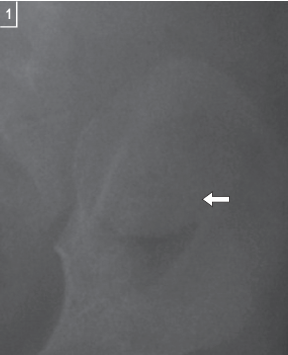

Fig. 56.1B

Este paciente presenta una masa de tejidos blandos que protruye hacia el interior del intestino grueso. El hallazgo es sutil (flecha). Puede haber signos de obstrucción proximal al nivel de la intususcepción.

La masa puede manifestarse como una ausencia de asas intestinales en esa región.

En ocasiones, puede observarse aire atrapado junto al segmento intestinal telescopado. También deben buscarse signos de perforación, aunque esta es una complicación poco frecuente.